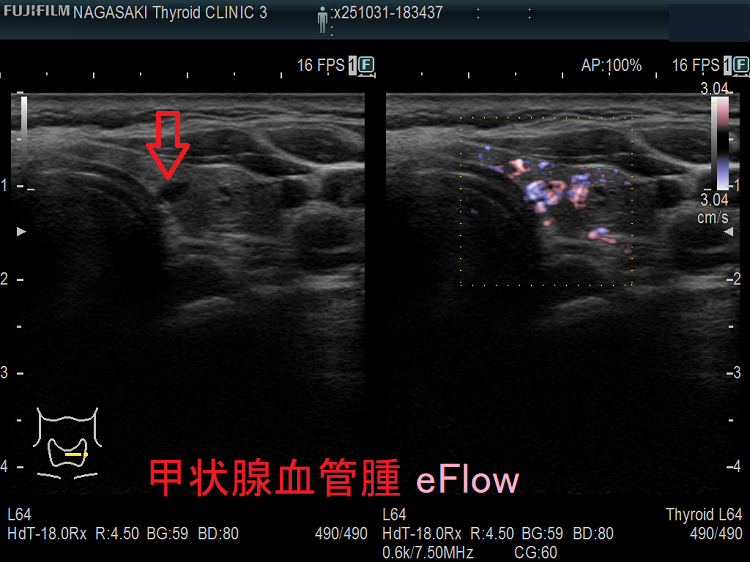

甲状腺に発生する血管腫は非常に稀で、日本の報告例もわずかです(日臨外会誌 72(3),579―583,2011)。

ケース①

ケース②

ケース③

甲状腺血管腫(拡大) ドプラーモード(eFlow);腫瘍内血管が3次元的に見え、毛玉の様。

ケース④

ケース⑤